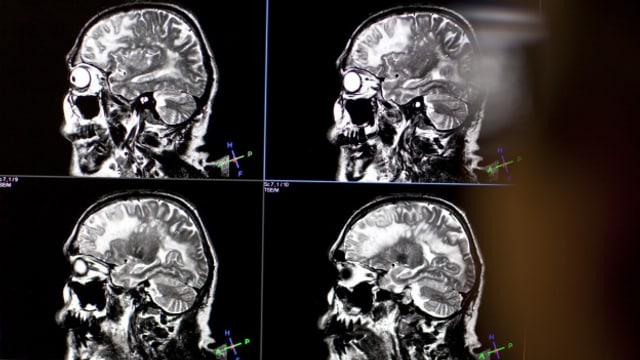

Oberbauch-MRT insbesondere MRCP Kernspintomographie der Gallenwege Hydro-MRT MRT-Sellink MRT des Dünndarms. Bei der MRT-Untersuchung Kopf macht der Arzt Schnittbilder vom knöchernen Schädel den Gefäßen sowie dem GehirnMRT-Untersuchungen laufen alle nach dem gleichen Prinzip ab. Um die Klarheit des Bildes zu verbessern werden spezielle Kontrastmittel verwendet Arzneimittel auf der Basis von paramagnetischem Gadolinium.